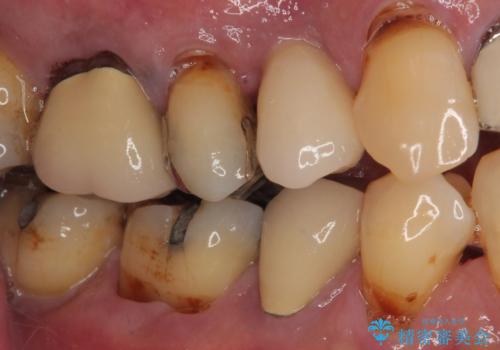

- 抜歯が必要なのでは?と近医で言われ、歯の保存を希望して来院された患者様です。

既に別の部位にインプラント治療を受けており、そのときの治療期間と苦労を鑑みて、何とか歯を残したいとのことで来院されました。

該当歯の状態としては何とか保存可能でしたが、予後不良のため、将来的にインプラント治療が必要となる可能性の高い状態でした。

当院での根管治療および歯周外科治療を併用した保存療法、並びに1DAYインプラントによる短期間インプラント治療の双方をご説明し、即日でインプラント治療を選択されました。

仮歯を用意した上で、抜歯即時埋入・即時荷重インプラントによる補綴治療を行うこととしました。